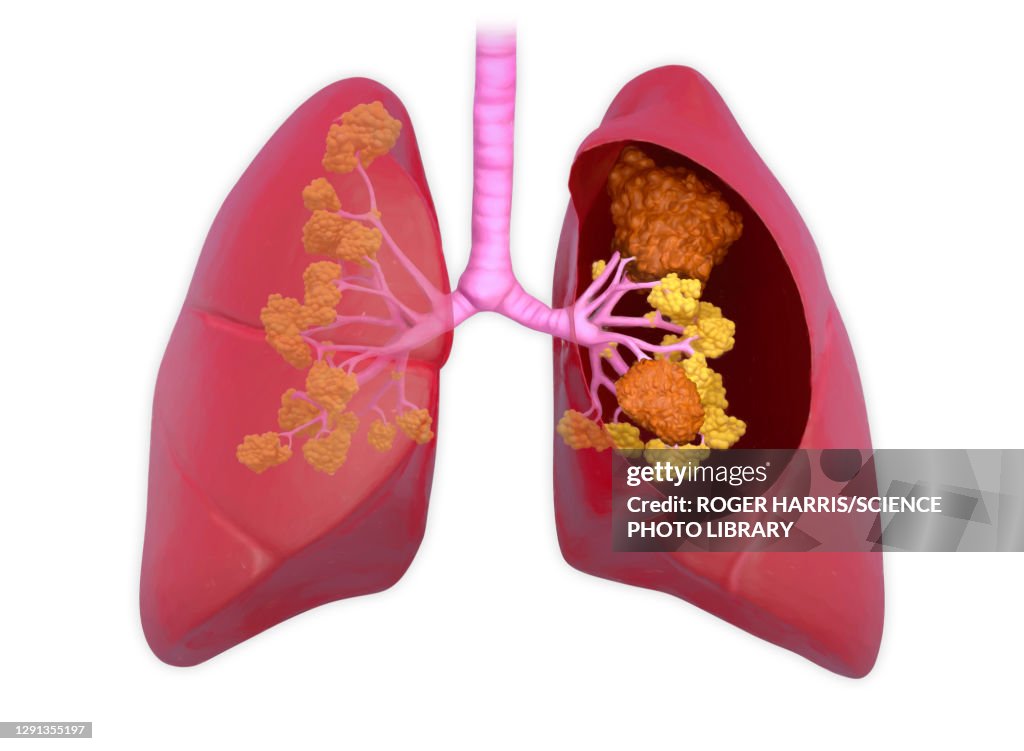

Lung cancer, illustration - Illustrazioni stock

Illustration of malignant (cancerous) tumours in a human lung. The lungs transport oxygen into the body through breathing. The trachea (windpipe) brings in air through tubular, tree-like branches called bronchi, which then branch into small bronchioles and finally into tiny microscopic sacs called alveoli. The lungs also eliminate carbon dioxide when breathing out. There are many different diseases of the lungs, including cancer.